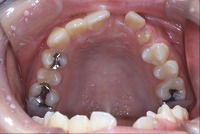

反対咬合と前歯が生えてこない事を主訴に来院された、10歳4か月の男の子です。診断「下顎骨の過成長による骨格性反対咬合で上顎正中の左方偏位と埋伏歯を伴う」1期治療で反対咬合の解消と埋まっていた前歯を牽引しました。